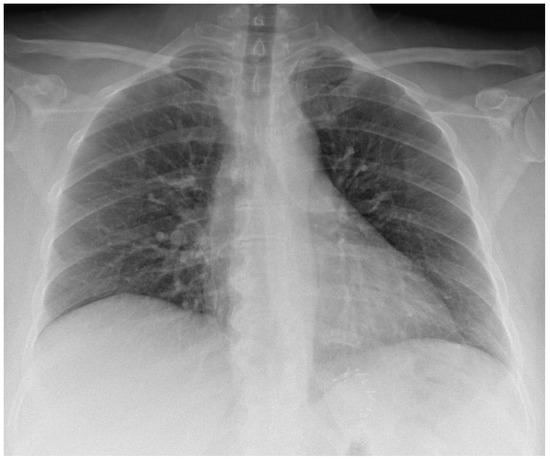

The chest radiography showed clear lungs and pleural spaces and regular cardio mediastinal counter (Figure 4), thus excluding tuberculosis and, implicitly, Pott’s disease and tuberculous spondylitis as causes of iliopsoas abscess. Despite a thorough CT scan examination, no evidence of colonic micro-perforations was found, leaving the cause uncertain. Additionally, the patient explicitly denied any past involvement in intravenous drug abuse. Furthermore, we requested an evaluation of the patient by the general surgeon on call, who recommended emergency hospitalization and surgical drainage, so she was transferred to the general surgery department.

Figure 4.

The chest radiography was performed in the ED.